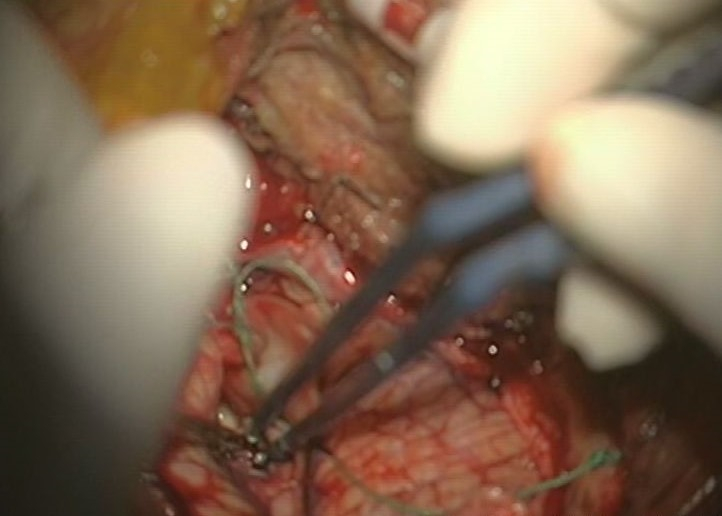

小腦腦梗塞手術

手術治療腦梗塞的

手術治療腦梗塞

手術治療中的腦梗塞